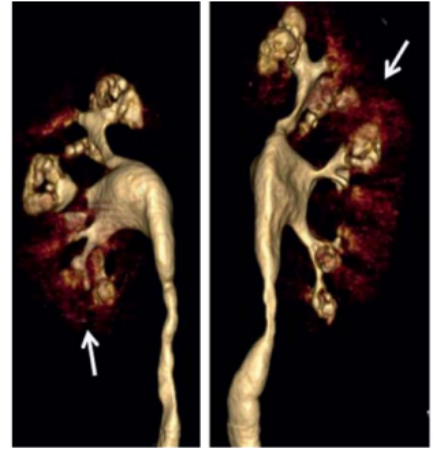

图4 MSK结石的增强CT排泄期相,可见囊状扩张的集合管被造影剂填充后出现“灯刷样"或"花束样"改变。

图5 MSK结石的增强CT三维重建,可见囊状扩张的集合管出现标志性的"花簇状"的景观。